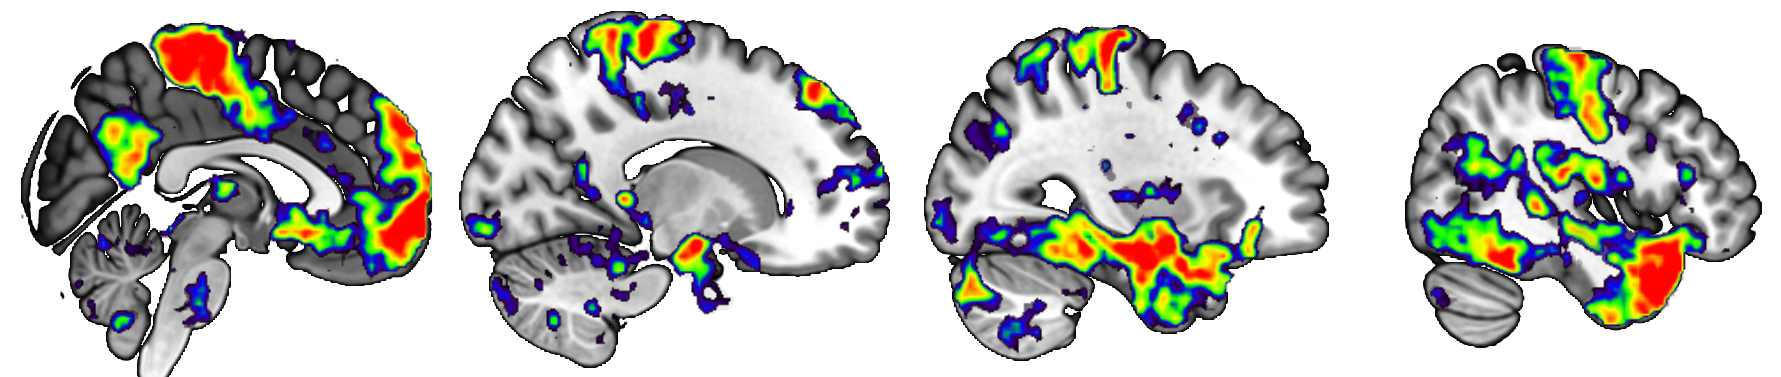

Ultra-high field data for cortico-subcortical network mapping in healthy controls

This repository consists of ultra-high field (7T), multi-echo functional connectivity (FC) data in 21 young, healthy adults. FC data acquired via fMRI are highly susceptible to influence from non-BOLD signals, such as physiological noise, head motion, and scanner effects (Buckner et al., 2013). Concerns about non-BOLD artifact have led to the increased usage of multi-echo imaging, which can be uniquely denoised with ME-ICA methods (Kundu et al., 2013). Additionally, ultra-high field imaging provides benefits over common 3T imaging by allowing for both greater image resolution and increased reliability of FC network results (Nemani & Lowe, 2021). The combination of multi-echo and ultra-high field imaging is ideal for mapping network properties of small, deep subcortical nuclei, such as those in the basal ganglia (Puckett et al., 2018).